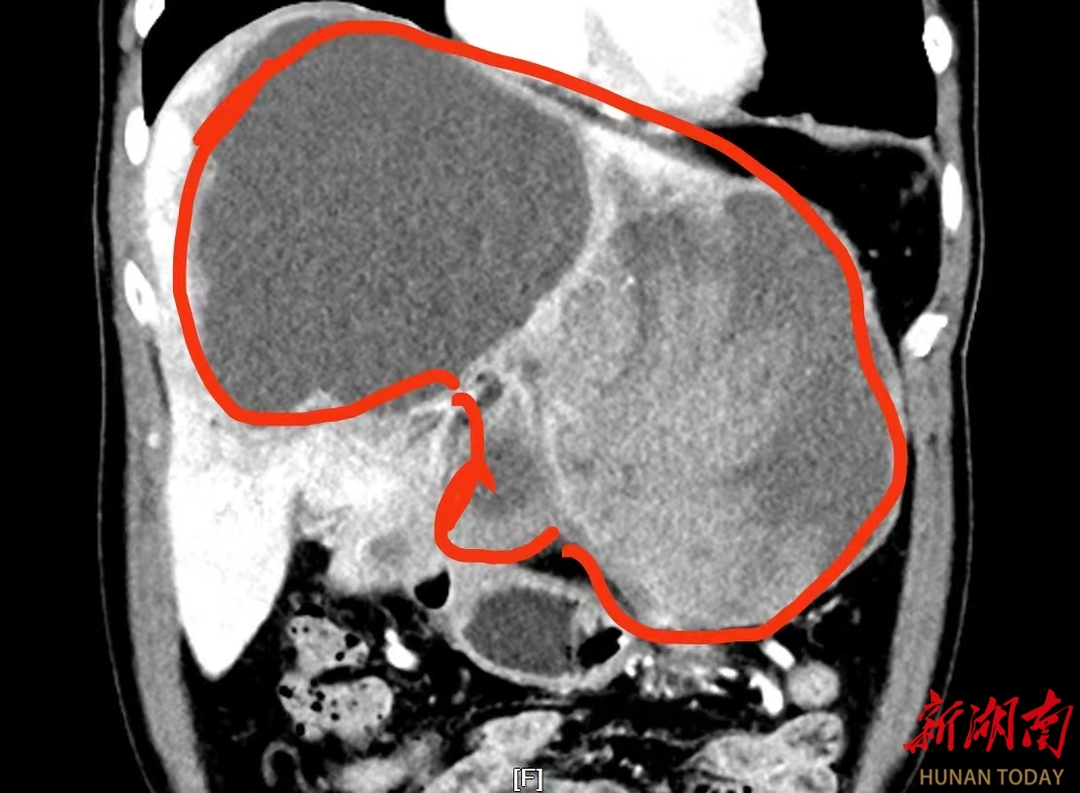

按照胃病治疗一段时间后,刘先生的症状不但没有好转,反而越发吃不下东西,只得利用国庆长假回到老家进一步检查。当CT结果出来后,刘先生如遭晴天霹雳——在他的胃和肝脏之间有一个22×21×14cm的巨大肿瘤!正是由于肿瘤挤压胃部,才导致他进食困难、吃啥吐啥。

影像资料显示:巨大的肿瘤占据了刘先生整个肝脏的三分之二。

入院进一步完善相关检查后,段小辉主任医疗小组与介入血管外科、消化内科、麻醉科等多学科专家,为刘先生进行了多学科会诊。专家团队一致认为:巨大的肿瘤占据了患者整个左肝以及右肝前叶,手术操作空间极为狭小;加上肿瘤内部出血超过2000毫升,面对血供如此丰富的肿瘤,手术操作必须十分精准,否则极可能引发术中大出血,甚至危及生命;此外,在术前的下肢深静脉血栓筛查中,患者被发现有右下肢静脉血栓。为防止术中、术后出现致命性肺栓塞,介入血管外科医生为他放置了血管滤器。